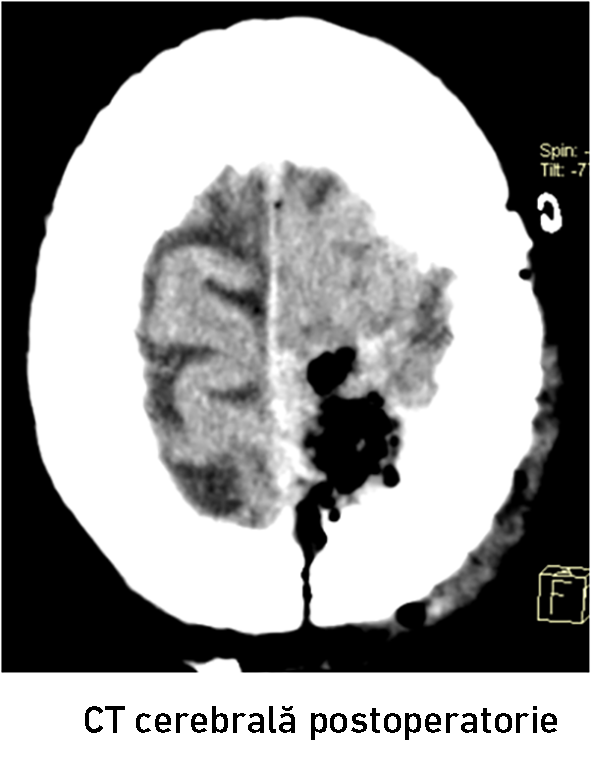

După 2 ore de la tratamentul endovascular, echipa chirurgicală a dat startul intervenției convenționale prin craniotomie osteoplastică. Grație embolizării preoperatorii, hemoragia intraoperatorie a fost redusă până la 500 ml. A fost realizată ablația totală macroscopică a meningiomului cu coagularea atașamentului dural, fapt confirmat prin CT cerebrală postoperatorie (fig. 8-10). Intervenția a fost efectuată de colaboratorii IMSP Spitalul Clinic Republican formată din conf. univ. d.ș.m. Eduard Eftodiev, dr. Alexandru Șumleanschi, dr. Iana Cotorcea, asistenta anestezistă Doina Dragan, asistentele de operație Maria Mutelică și Macela Cucheev. Toate obiectivele propuse au fost realizate cu succes de către echipa neurochirurgicală. Bolnava a fost externată la ziua 9-a postoperator în stare satisfăcătoare. Starea pacientei s-a ameliorat după tratamentul combinat : a regresat hemipareza în membrele drepte, pacienta devenind autonomă (Karnofsky PS 70%). Cu toate că bolnava a recuperat spectaculos forța în membrele hemicorpului drept, a fost recomandat continuarea tratamentului de recuperare şi neuroreabilitare.

După 2 ore de la tratamentul endovascular, echipa chirurgicală a dat startul intervenției convenționale prin craniotomie osteoplastică. Grație embolizării preoperatorii, hemoragia intraoperatorie a fost redusă până la 500 ml. A fost realizată ablația totală macroscopică a meningiomului cu coagularea atașamentului dural, fapt confirmat prin CT cerebrală postoperatorie (fig. 8-10). Intervenția a fost efectuată de colaboratorii IMSP Spitalul Clinic Republican formată din conf. univ. d.ș.m. Eduard Eftodiev, dr. Alexandru Șumleanschi, dr. Iana Cotorcea, asistenta anestezistă Doina Dragan, asistentele de operație Maria Mutelică și Macela Cucheev. Toate obiectivele propuse au fost realizate cu succes de către echipa neurochirurgicală. Bolnava a fost externată la ziua 9-a postoperator în stare satisfăcătoare. Starea pacientei s-a ameliorat după tratamentul combinat : a regresat hemipareza în membrele drepte, pacienta devenind autonomă (Karnofsky PS 70%). Cu toate că bolnava a recuperat spectaculos forța în membrele hemicorpului drept, a fost recomandat continuarea tratamentului de recuperare şi neuroreabilitare.